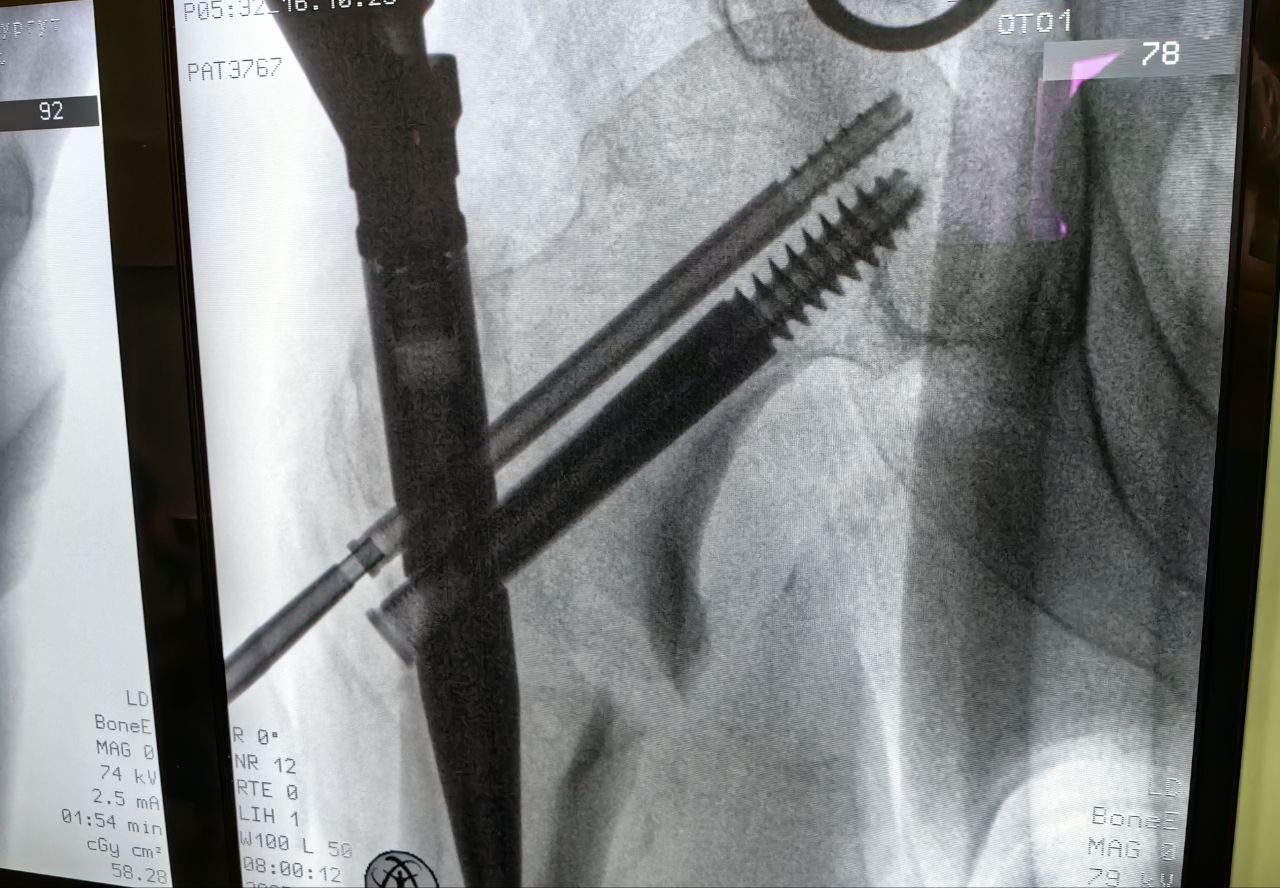

Под постоянным контролем электронно-оптического преобразователя пациенту в место перелома бедренной кости установили интрамедуллярный штифт, которым зафиксировали отломки в нужном положении. Операция выполняется закрытым доступом, через три разреза. Самый большой из них – всего 2 сантиметра.

Для этого больного травматологи-ортопеды выбрали органосохраняющую малотравматичную методику – блокируемый интрамедуллярный остеосинтез.